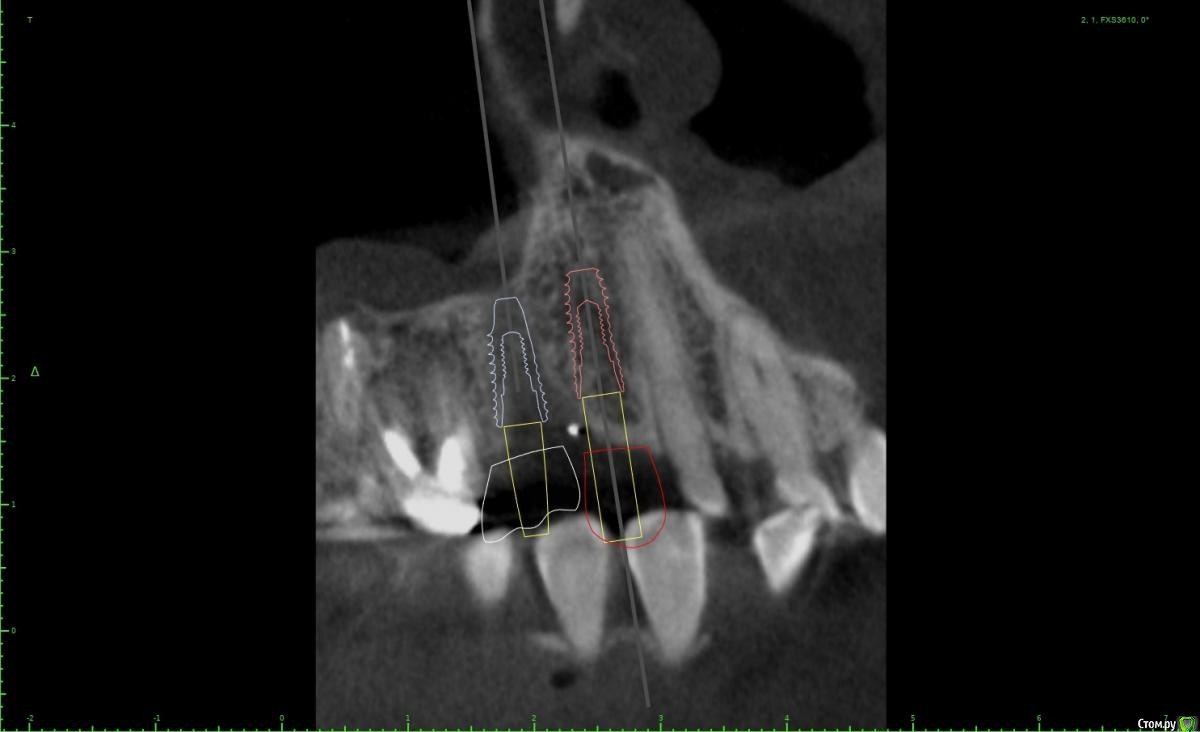

Женька Опубликовано 28 января, 2021 Поделиться Опубликовано 28 января, 2021 Что-то все спрашивают про консоли на имплантатах в области премоляров! Спрошу и я тоже.Коллеги как бы поступили в этом случае?Сам склоняюсь к консоли, но переживаю, что надо бы имплантат пошире, чтобы нагрузку нёс за двоих спокойно. Вариант с двумя винтами не нравится потому как тонковато (не очень) в области 1.4 и необходима редукция около 3мм кости. Ссылка на комментарий

Irouil Опубликовано 28 января, 2021 Поделиться Опубликовано 28 января, 2021 ИМХО два винта, но давайте с замерами тогда Ссылка на комментарий

Женька Опубликовано 1 февраля, 2021 Автор Поделиться Опубликовано 1 февраля, 2021 ИМХО два винта, но давайте с замерами тогдаДа, наверное вы правы, два по 3.6 проходят Ссылка на комментарий

Irouil Опубликовано 1 февраля, 2021 Поделиться Опубликовано 1 февраля, 2021 Я бы развел винты побольше, лучше ближе к зубам чем друг к другу, кроме того дистальный имплант можно сместить немного небнее Ссылка на комментарий